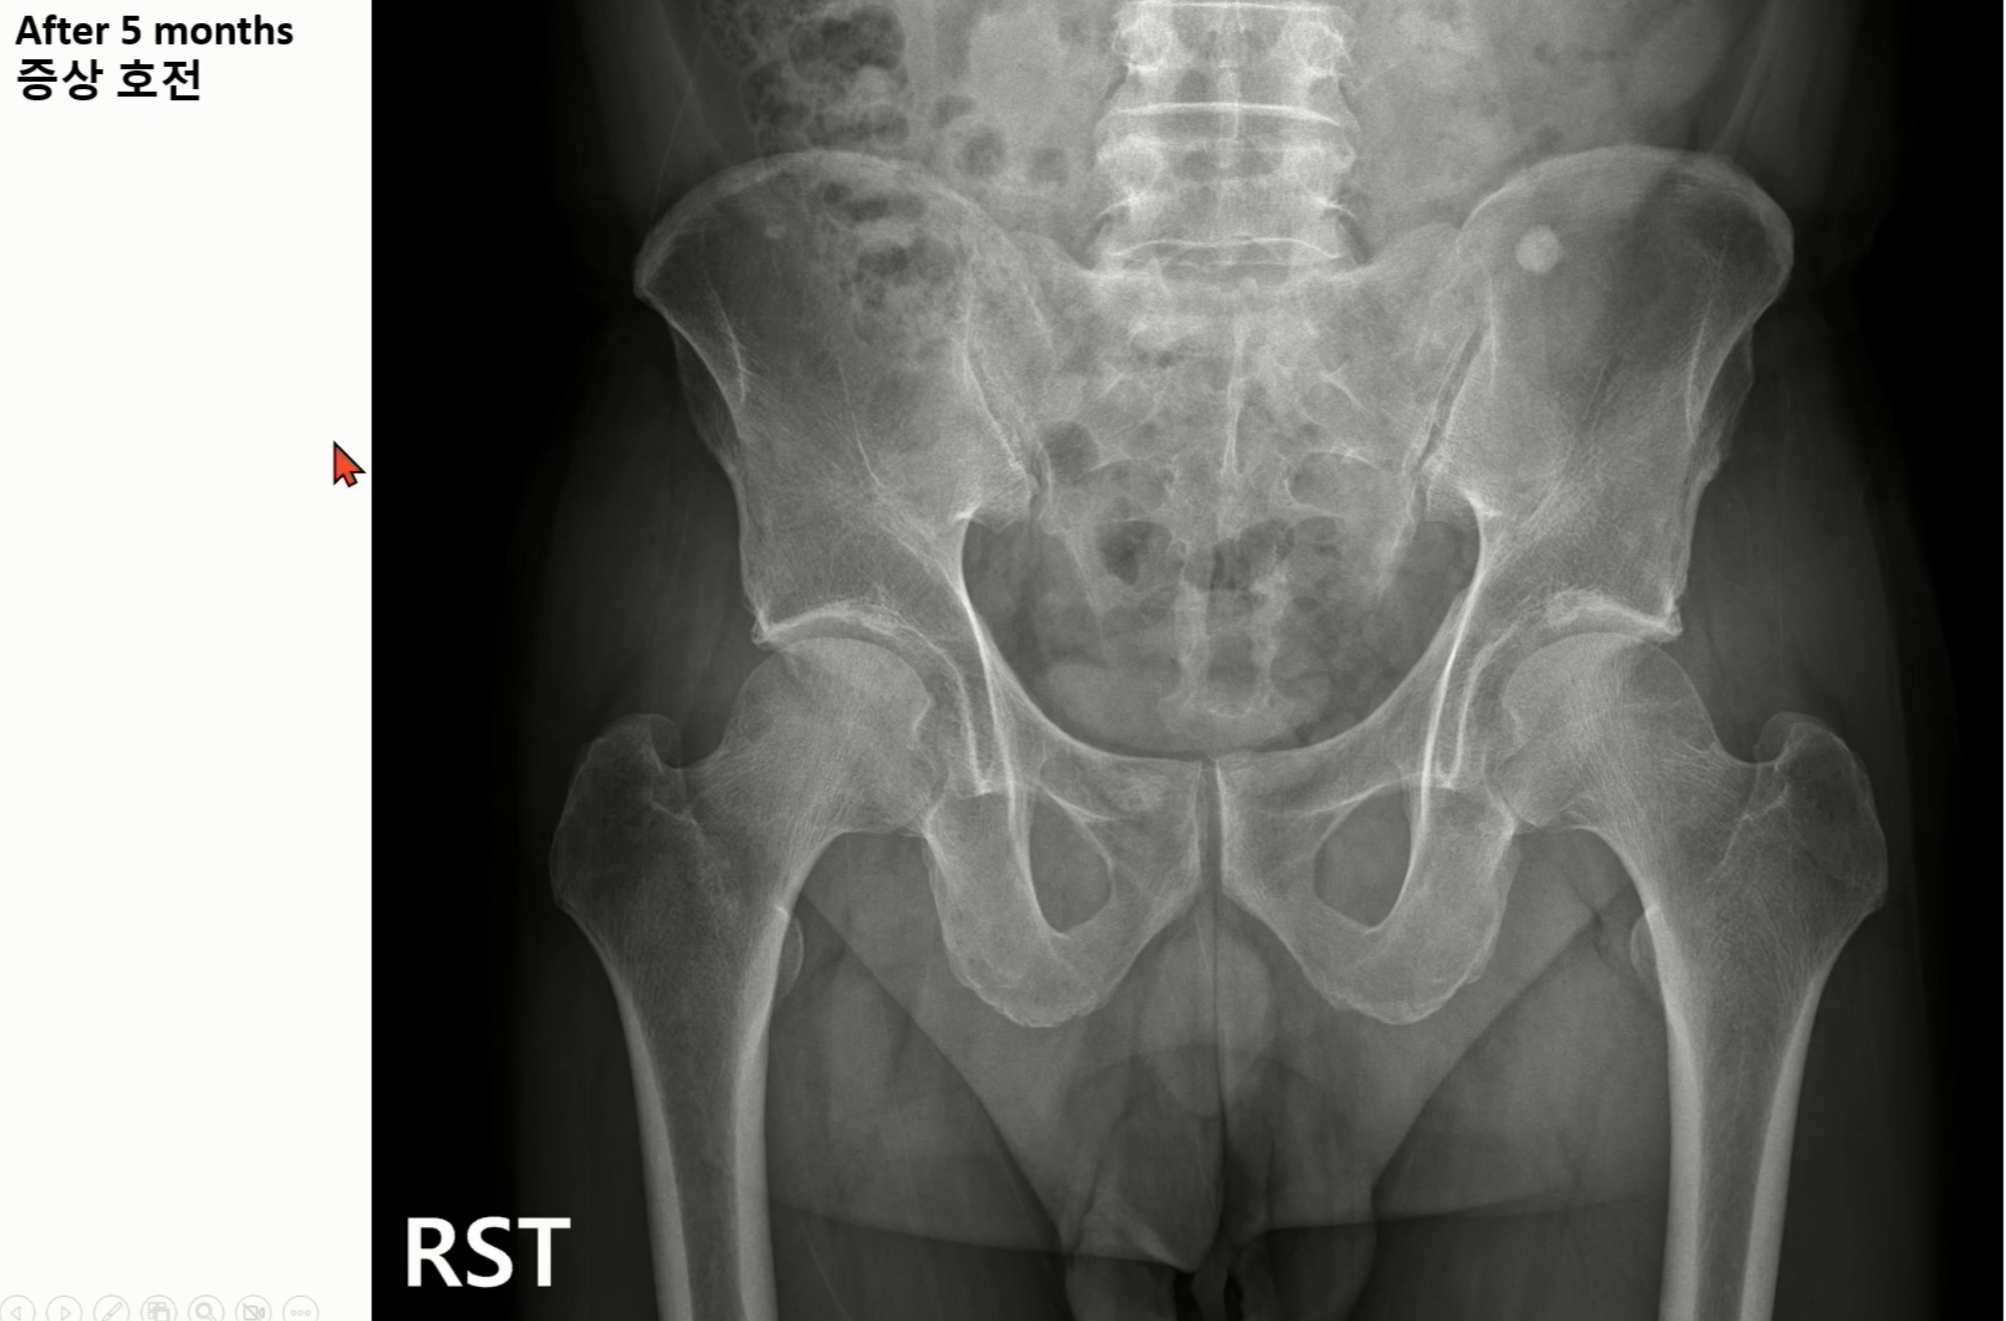

엑스레이상 우측 고관절에서 비구 이형성증에 합당한 소견을 보였습니다.

실제 케이스입니다.